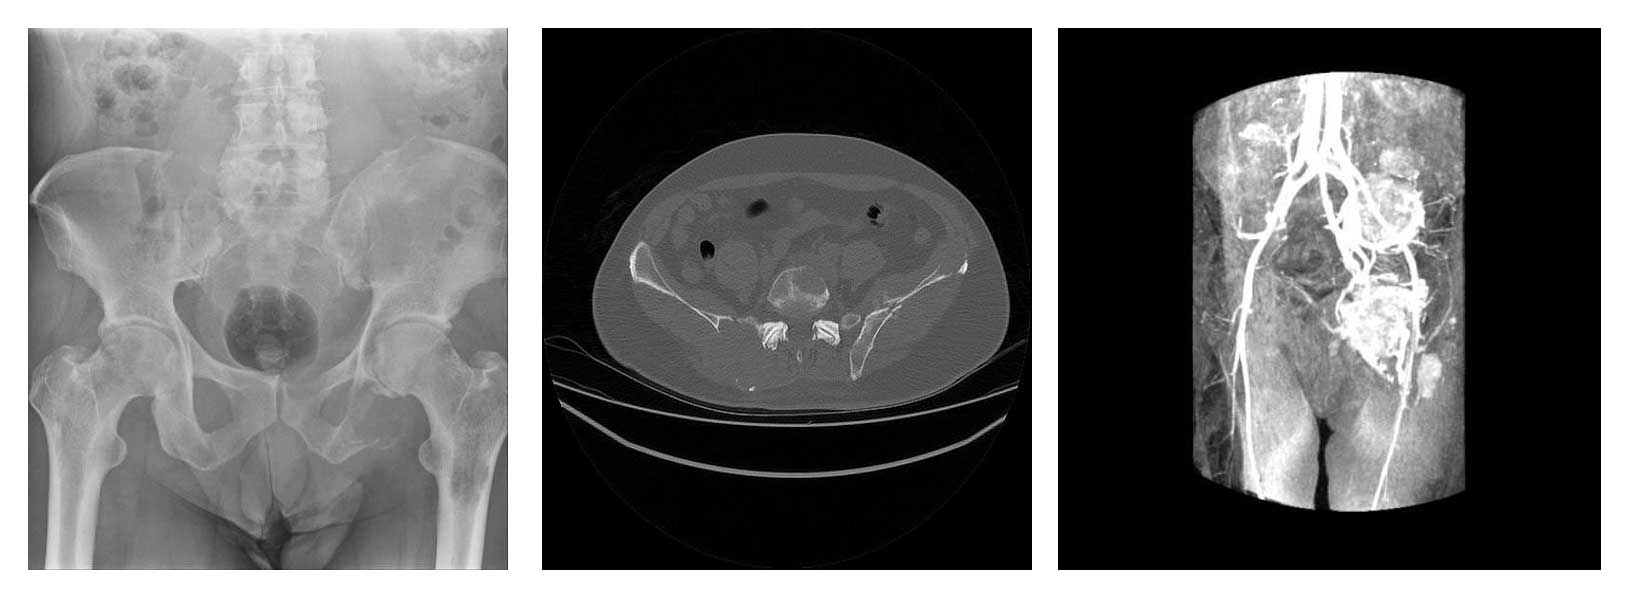

Ameliyat Öncesi: Pelvis röntgeninde birçok metastaz odağı, Tomografide ciddi harabiyet ve kırık, anjiyografide metastaz odaklarında yoğun kanlanma görülmekte.